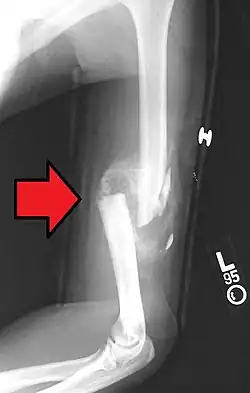

A transverse fracture of the humerus shaft -

A spiral fracture of the distal one-third of the humerus shaft -